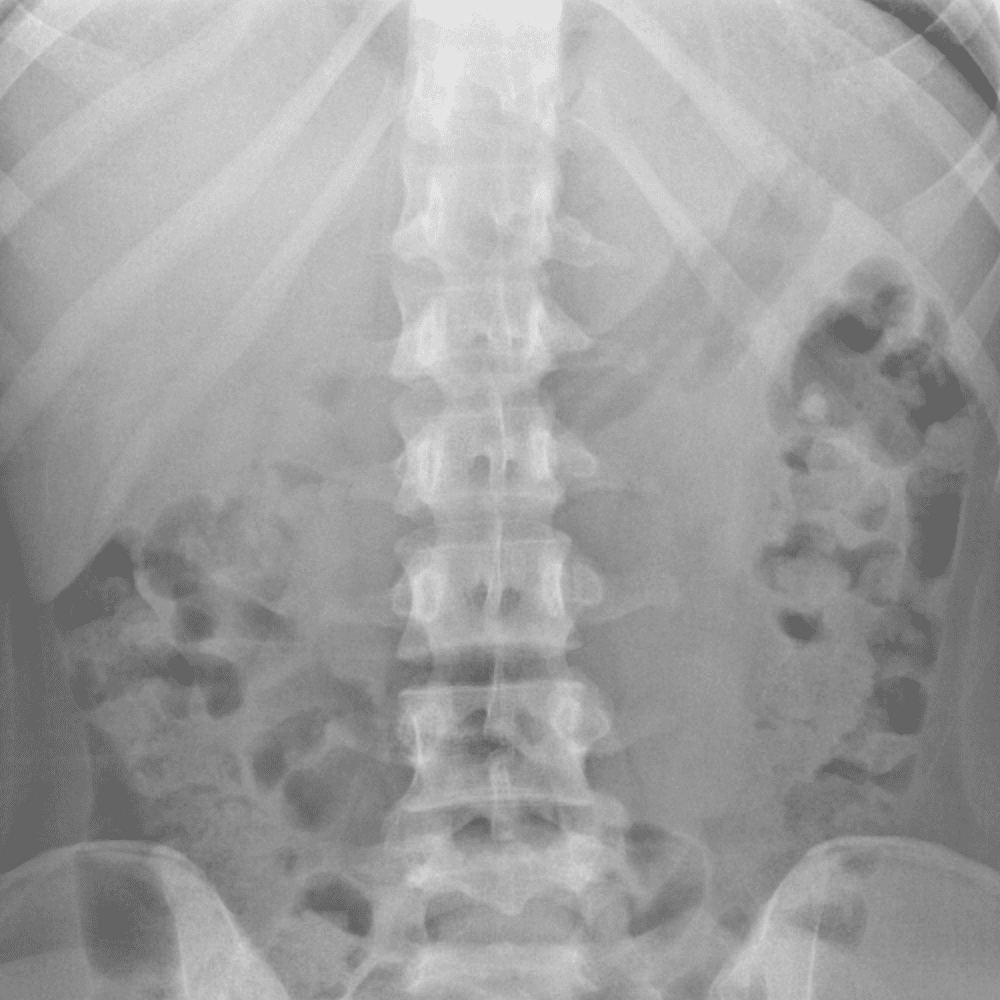

Peds Abdomen

Practice

Simulates call by including subtle or difficult cases and some normals.

30 cases